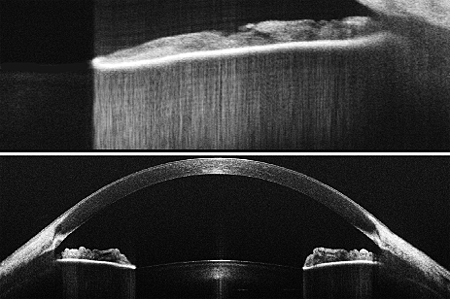

A new system from optical imaging company Wasatch Photonics could provide greater contrast and deeper sub-surface imaging than competitive techniques, the developer claims. The system could be used in the fields of material inspection and medical diagnosis, including cardiovascular and dermatological research, leading to faster and more accurate analyses.

Wasatch Photonics, based in Logan, UT, USA, has developed a spectral-domain optical coherence tomography system in the 1300 nm wavelength range. The Utah-headquartered firm also has locations in Research Triangle Park in North Carolina and Purdue Research Park.

Nishant Mohan, director of product management at Wasatch Photonics, said the new system showcases the company's abilities: "It brings together our strengths in optical engineering, software development and manufacturing demonstrated in earlier generations of 800nm systems. A commercially available 1300nm engine that can operate at the rate of 70 kHz A-lines should open several new applications for optical coherence tomography."